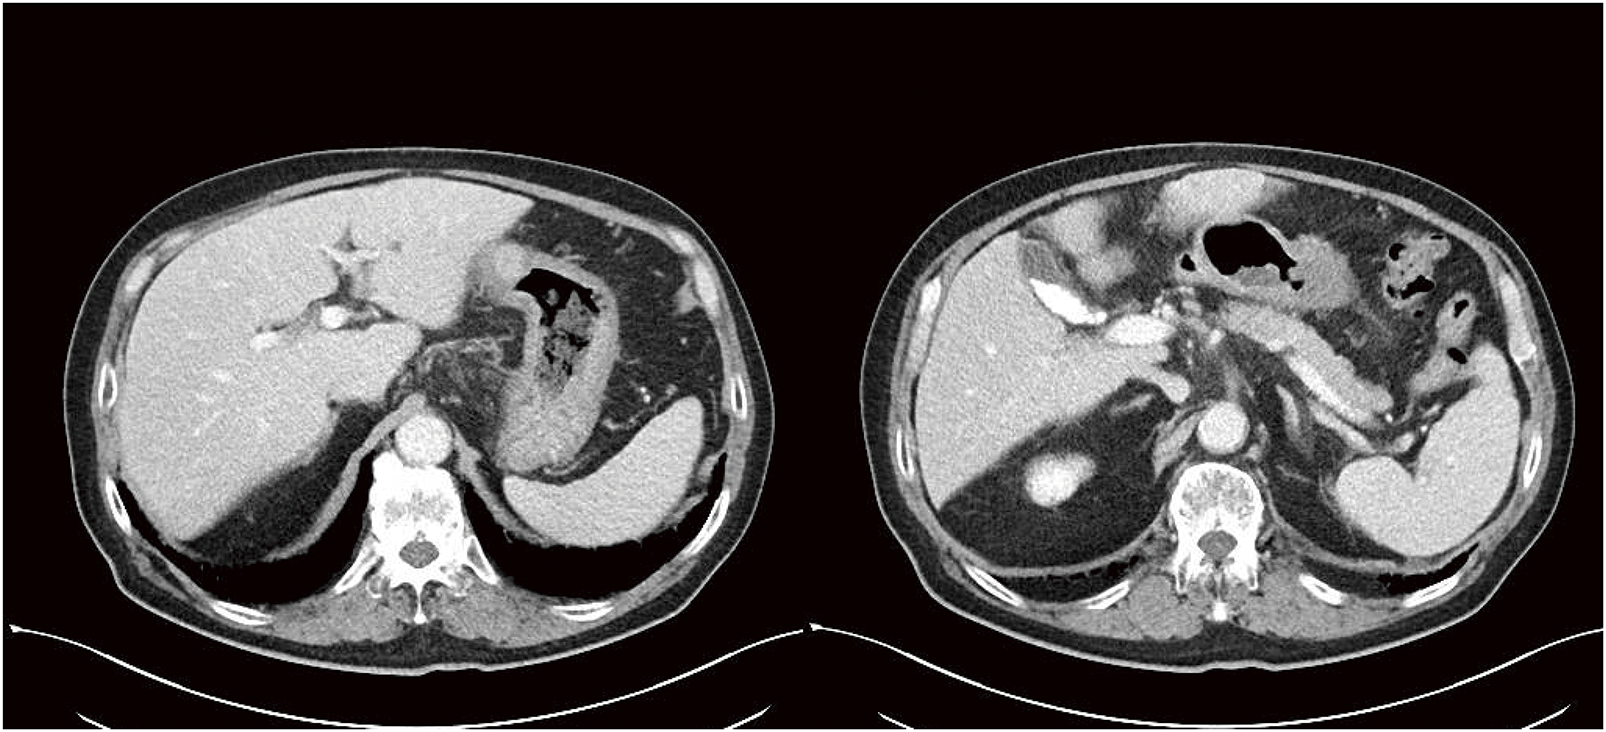

A 74-year-old male visited a hospital complaining of fatigue and was found to have anemia with a hemoglobin level of 5.0 g/dL. He was referred to our hospital for further evaluation and treatment. His past medical history included postoperative abdominal aortic aneurysm, angina pectoris, hypertension, and diabetes mellitus. Upper gastrointestinal endoscopy (Fig. 1) revealed a 50-mm Type 3 tumor in the greater curvature of the lower body of the stomach. Biopsy results confirmed the presence of adenocarcinoma. Examination of the biopsied tissue revealed tumor cells with clear cytoplasm proliferating in a papillary pattern, which warranted further immunohistochemical analysis. The immunohistochemical results were positive for spalt-like transcription factor 4 (SALL-4) and negative for both AFP and glypican-3 (GPC3) (Fig. 2), which facilitated a diagnosis of GAED. As shown in Table 1, blood tests revealed no elevation of tumor markers, including AFP. Contrast-enhanced computed tomography (CT) (Fig. 3) revealed gastric wall thickening, suspected pancreatic invasion, and peritoneal dissemination nodules. The patient was diagnosed with unresectable advanced gastric cancer. During SOX therapy, molecular markers of this tumor were determined to be negative for HER2, negative for claudin (CLDN) 18.2, with a combined positive score (CPS) of >5, and high microsatellite instability (MSI). Based on these findings, the introduction of ICIs was deemed desirable, and SOX plus nivolumab was initiated. After 7 courses of SOX plus nivolumab, upper gastrointestinal endoscopy (Fig. 4) showed marked tumor shrinkage. After 9 courses, contrast-enhanced CT (Fig. 5) confirmed the reduction of the primary lesion and the disappearance of the peritoneal dissemination nodules. One year and two months after the initial diagnosis, staging laparoscopy was performed, revealing no evidence of peritoneal dissemination or metastasis, and negative peritoneal cytology (CY0) was confirmed intraoperatively. The posterior wall of the stomach showed adhesion to the pancreas, making dissection difficult, but no apparent pancreatic invasion was observed. CS was considered feasible, and laparoscopic distal gastrectomy with D2 lymph node dissection and Roux-en-Y reconstruction was performed. The patient developed a postoperative pancreatic fistula, but it improved with conservative treatment, and he was discharged on postoperative day 36. Pathological examination (Fig. 6) revealed a Type 5 tumor measuring 44 × 30 mm in the anterior wall to the greater curvature of the middle and lower stomach, with negative resection margins. Tumor cells were distributed in the submucosal tissue or more profoundly, but no cancer cells were found in the superficial mucosa. Although the tumor cells were degenerated because of pharmacotherapy, most were SALL-4-positive, consistent with GAED. The depth of invasion was T2 (muscularis propria [MP]). Vascular invasion and lymphatic invasion were observed. A total of 14 lymph nodes were dissected, but no metastasis was observed, and there were no scars from metastasis that had disappeared with pharmacotherapy. The final pathological diagnosis was gastric cancer of the middle and lower stomach, anterior wall to greater curvature, Type 5, GAED, ypT2(MP), INFa, Ly1a, V1a, pPM0, pDM0, ypN0, ycM0(H0, P0, CY0), and ypStage IB. The effect of chemotherapy was classified as Grade 2a. Following surgery, adjuvant chemotherapy with S-1 monotherapy was initiated; however, 4 months postoperatively, bilateral inguinal hernias were identified. An abdominal CT scan (Fig. 7A) revealed no peritoneal dissemination nodules, although ascites were present. Cytological analysis of the ascitic fluid classified it as Class II, with no other identifiable causes for the ascites. Additionally, elevated cancer antigen 125 (CA125) levels suggested a potential recurrence of peritoneal dissemination. Treatment with nivolumab monotherapy was subsequently resumed. After 17 cycles, contrast-enhanced CT (Fig. 7B) indicated a reduction in ascites, and the symptoms associated with the inguinal hernias had resolved. CA125 levels also showed a trend toward normalization, and the patient was evaluated as having achieved a partial response (PR). Figure 8 summarizes the clinical course of this case. The patient has continued nivolumab monotherapy and has currently achieved a survival period of 29 months since the initial diagnosis.

CT, computed tomography

CT, computed tomography